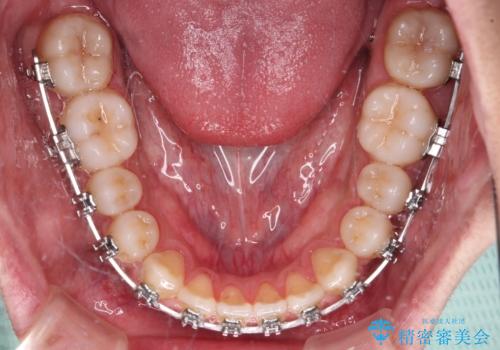

- メタルブラケット

- 治療期間

- 10ヶ月

骨格的な左右差も顕著であったため、正中は合わず、上下前歯の一部が接触しない咬み合わせとなることが予想されましたが、正中はもともとのズレが小さかったことから、合わせることができました。

治療期間も10か月間という短期間で終了し、患者様には大変満足していただきました。